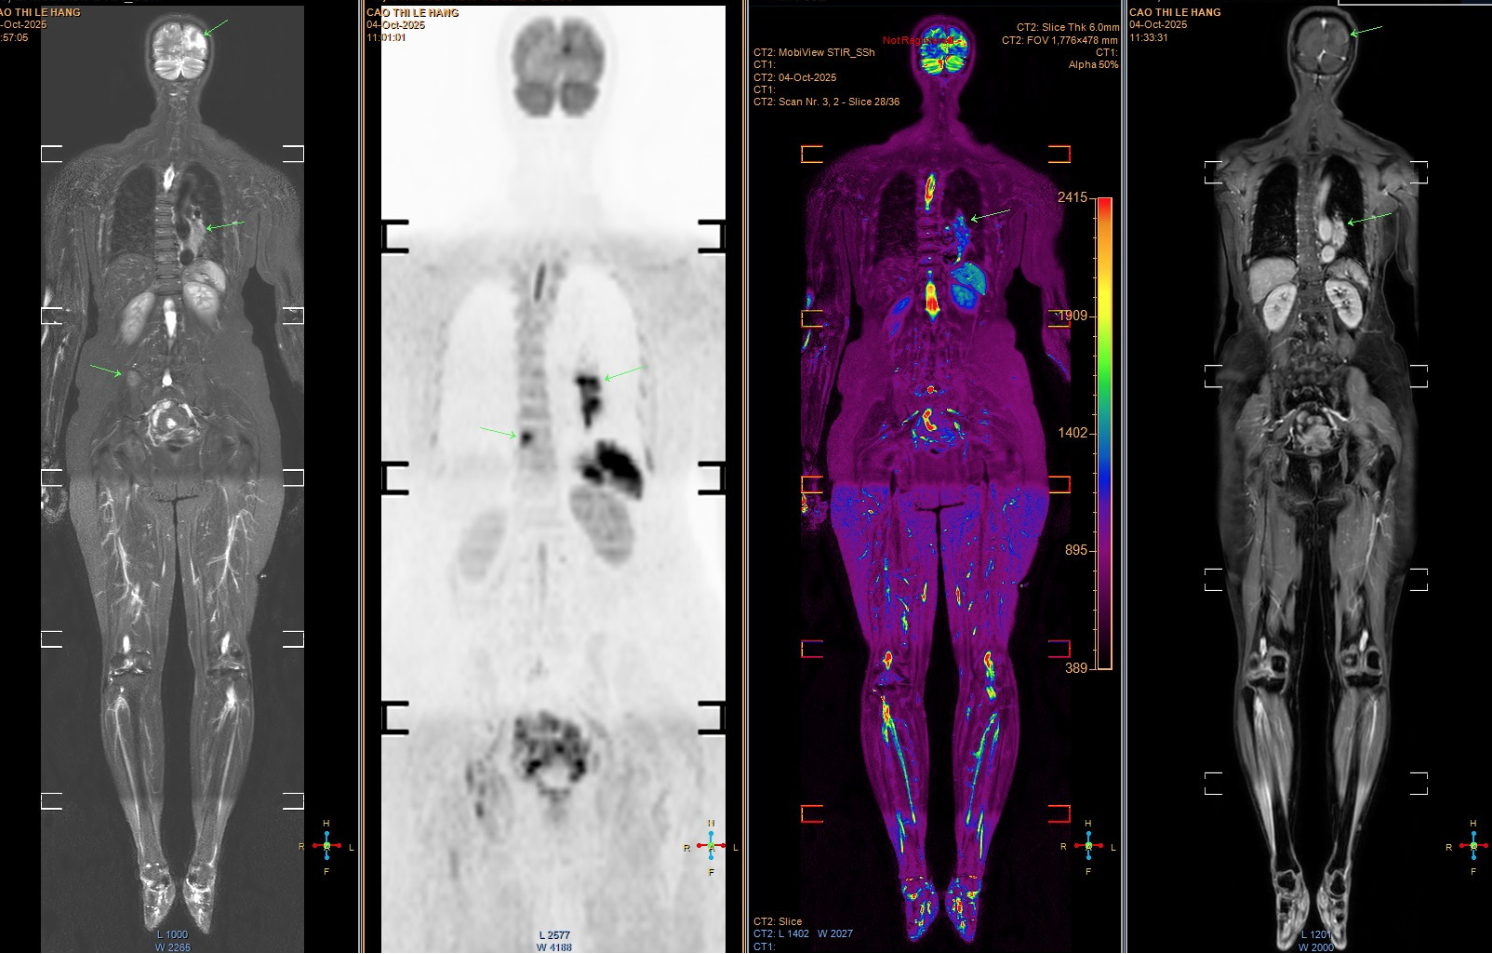

Hình ảnh chụp tổn thương di căn của bệnh nhân. (Ảnh: Bác sĩ cung cấp)

Tuy nhiên, các triệu chứng ngày càng nhiều và nặng hơn, bệnh nhân mới chịu đi khám sức khỏe. Kết quả chụp MRI cho thấy nhiều ổ tổn thương di căn dạng biểu mô tuyến. Khi chụp CT ngực, bác sĩ phát hiện một khối u lớn ở đáy phổi trái, xác định là ung thư phổi giai đoạn muộn, đã di căn sang nhiều cơ quan, trong đó có não bộ. Tiên lượng bệnh rất xấu.